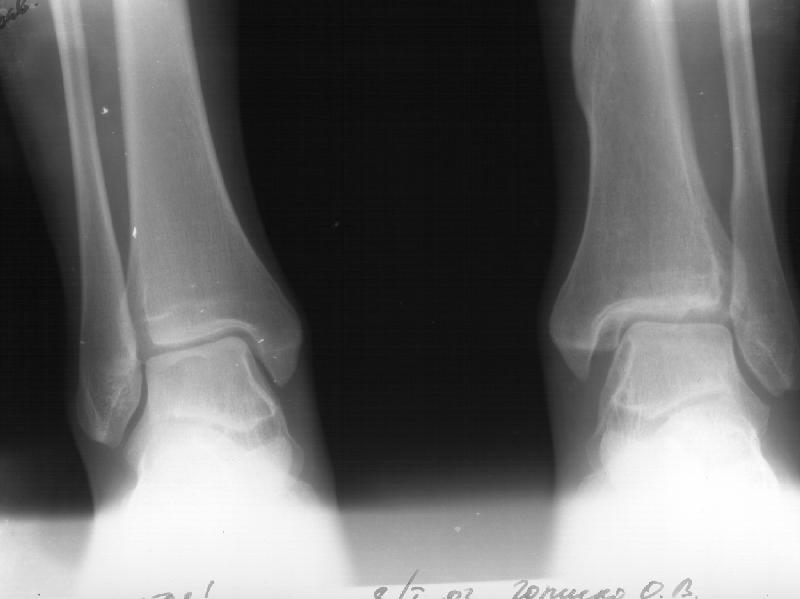

Отправитель: Й. Воск 19 Январь 2003, 22:29

Я пометил линию перелома черной линией.

К сожалению на последних присланных срезах КТ нет более низкого, через таран, среза, который был на прежнем майле. На XR я попытался показать

стержень внутри сустава и то как он раскрывает пространство между тараном и мед. малеолом.